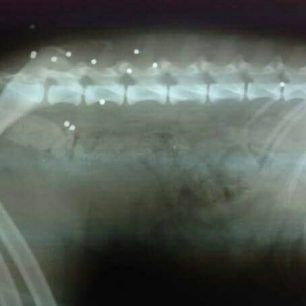

Κατά την εξέταση του ζώου και όπως φάνηκε και από την ακτινογραφία τα τραύματα προήλθαν από σκάγια. Η κα Μαυροματάκη, η οποία φιλοξενεί το αδεσποτάκι καθώς χρειάζεται να ολοκληρώσει την φαρμακευτική αγωγή, απευθύνει έκκληση για την υιοθεσία του σκύλου, που είναι εξαιρετικά ήσυχος και υπάκουος ώστε να μην ξανακινδυνέψει στους δρόμους. Μάλιστα η εκπρόσωπος του συλλόγου με ανάρτηση της στο facebook ζητάει από τον Δήμο Πλατανιά να φτιάξει ένα προσωρινό χώρο φιλοξενίας για τα αδέσποτα ώστε εκεί να μένουν τα ζώα που στειρώνονται και όσα δεν υιοθετούνται και μετά τον εμβολιασμό να επανατοποθετούνται. Αν θα θέλατε να υιοθετήσετε τον σκυλάκο που αυτή τη φορά γλύτωσε επικοινωνήσετε με την κα Μαυροματάκη μέσω facebook εδώ.